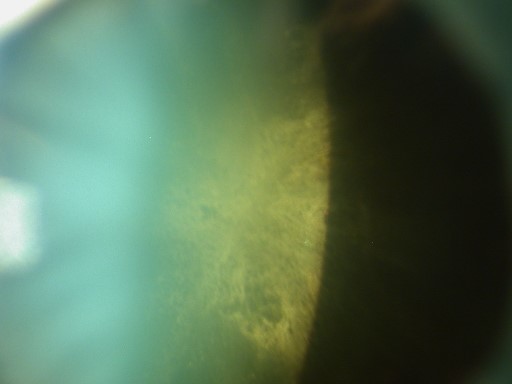

Son œil droit est blanc et indolore. On retrouve une acuité visuelle chiffrée à moins de 0,5/10e à droite contre 8/10e à gauche. Il n’y a pas de notion de traumatisme.

L’examen du RPM est important car il peut orienter vers un diagnostic grave (OACR/NOIAA), mais c’est l’imagerie et la biologie qui motiveront la mise en place du traitement en urgence.